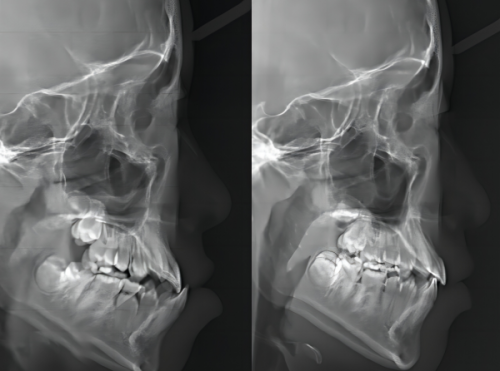

硬件方面,医院主打“科研 + 临床双轨发展”,引进德国卡瓦CBCT、西诺德数字化种植系统等设备,开设种植、正畸、修复、牙周、儿牙等8大专科,覆盖全年龄段口腔需求。软件方面,医院拥有专精的医生团队,像谢小军院长是隐适美/舌侧矫治认证医生,擅长隐形矫正;金钟球院长北京大学口腔医学校 + 首尔大学联合培养,种植经验多。